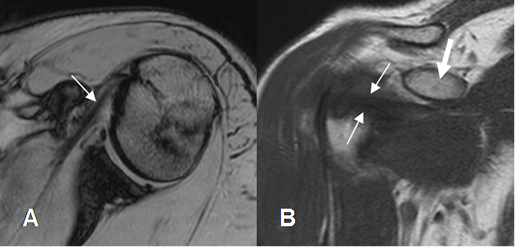

Fig 17. Tendones normales del manguito rotador.

RM sagital en T2. SE: Supraespinoso. IE: Infraespinoso. SB: Subescapular. RM: Redondo menor. BI: Cabeza larga del bíceps.

Fig 18. Angulo mágico.

A: RM coronal en T1. Tendón supraespinoso con aumento de su señal.

B: RM coronal en T2. Tendón hipointenso y normal, por el efecto del ángulo mágico.

Fig 19. Tendinitis del supraespinoso.

A: RM coronal en T1. Aumento en la señal del tendón supraespinoso.

B: RM coronal en T2 y C: RM coronal en STIR. El supraespinoso es hiperintenso, irregular y rodeado por líquido, por tendinitis